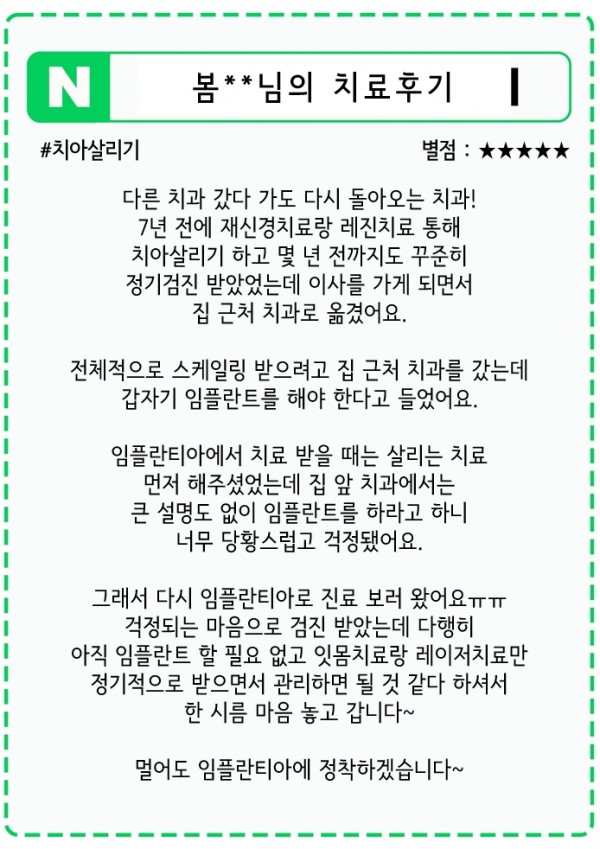

실제 후기로 확인하는 만족도